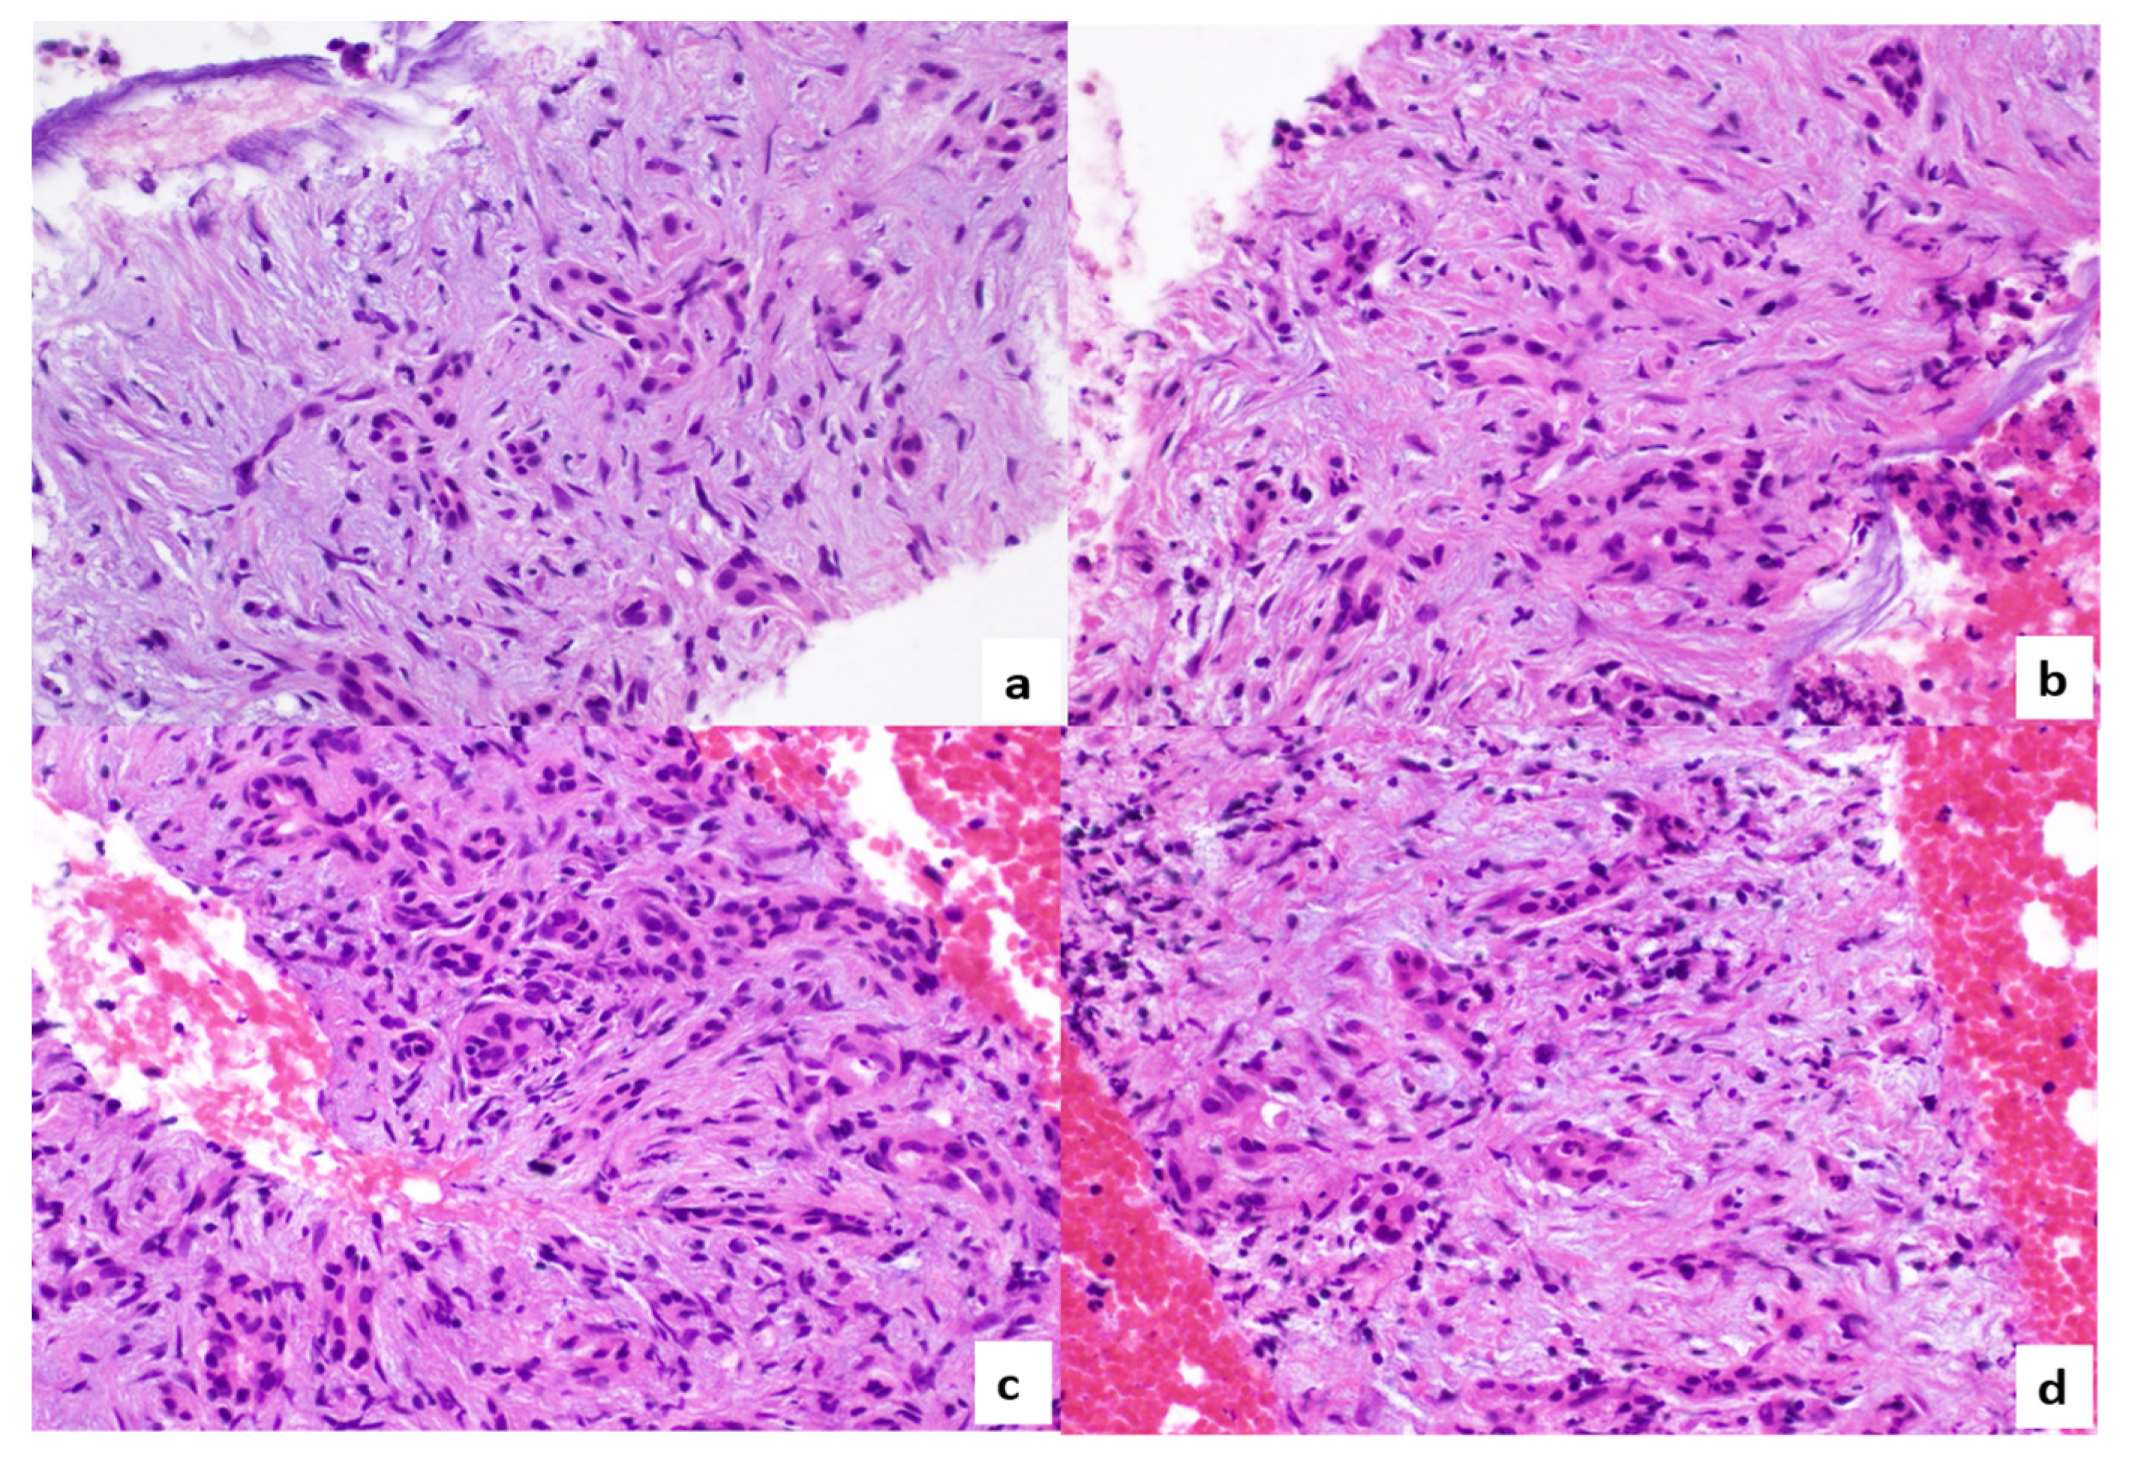

2. Case Report

3. Discussion